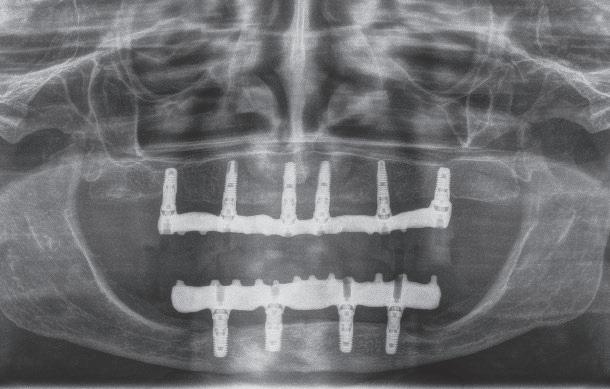

Esta es una pregunta con difícil respuesta. Realmente el límite lo ponen los factores anteriormente nombrados. Cada uno de ellos debería analizarse en conjunto para decidir si un caso es o no susceptible de regeneración. Si nos centramos específicamente en los factores del defecto (número de paredes, ángulo del defecto, profundidad del defecto, movilidad dental, lesión endo-periodontal), ninguno de ellos per se puede ser suficiente como para justificar la imposibilidad de realizar una regeneración periodontal con el objetivo de mantener el diente en boca. Ni siquiera la inserción dental remanente, por mínima que sea, incluso llegando a ser nula. El caso que presento (caso 3) es un ejemplo de ello. Mujer de 68 años, exfumadora hace 20 años de 10 cigarrillos/día, sin patologías sistémicas. Acude a nuestra clínica con el siguiente motivo de consulta: “Tengo mucho miedo de perder mis dientes. Llevo muchos años con movilidad y me gustaría que hicieran lo posible por evitar extracciones”. La paciente presentaba una periodontitis estadio III, grado A10; con vitalidad negativa en el diente 31 (fig. 3.1). Tras su diagnóstico completo, decidimos hacer un tratamiento periodontal básico e instrucciones de higiene oral (fig. 3.2). Posteriormente derivamos el caso a nuestro endodoncista, el doctor Luis Costa, quien comenzó el tratamiento endodóntico del diente 31 colocando hidróxido de calcio y ferulizando el diente 31 al 32. Una semana después finalizó la endodoncia del mismo con su correspondiente obturación y sellado coronal. Tras un periodo de cuatro meses, la paciente seguía presentando sondajes periodontales muy profundos en todo el 5º sextante. La radiografía periapical del 31 a los cuatro meses mostraba la ausencia de regeneración del defecto con el tratamiento realizado hasta la fecha. Incluso se podía apreciar un posible desplazamiento del ápice del diente 31 (fig. 3.3). Dada la situación clínica, decidimos hacer un tratamiento regenerativo de todo el sextante mediante una técnica quirúrgica de preservación de papila modificada36 aplicando únicamente proteínas derivadas de la matriz del esmalte (fig. 3.4). El problema surgió cuando la ferulización del 31 se rompió durante el raspado y alisado radicular del diente (fig. 3.5). Dado que el tratamiento regenerativo estaba destinado a todo el sextante y no solo al 31 (fig. 3.6), decidimos seguir adelante con nuestra intervención con la intención de mantener “todos” sus dientes. Colocamos el diente avulsionado en suero fisiológi-

RFIG. 3.1

co y continuamos con el desbridamiento de todo el área a tratar. Al finalizar el raspado y alisado radicular, eliminamos los dos últimos milímetros del ápice del incisivo avulsionado (fig. 3.7) y lo volvimos a reponer en su sitio ferulizándolo en una posición ligeramente más apical a la original, con la intención de aproximar la raíz al defecto y facilitando la ausencia de oclusión del susodicho diente (fig. 3.8). A continuación, aplicamos EDTA al 24 % durante 2 minutos, lavamos, secamos y aplicamos proteínas derivadas de

RFIG. 3.2

la matriz del esmalte sobre las superficies radiculares de los dientes a tratar (fig. 3.9). Finalmente, suturamos consiguiendo un cierre por primera intención. Retiramos la sutura a las dos semanas y pasamos a la paciente a fase de mantenimiento periodontal. Como en todos los casos de regeneración periodontal que tratamos, realizamos un mantenimiento periodontal de la zona regenerada al mes, 2 meses, 3 meses, 6 meses, 9 meses y 12 meses. En la cita de los 6 y 12 meses aprovechamos para hacer un man-

tenimiento periodontal de toda la boca. Así, al cumplir un año desde la regeneración, realizamos una reevaluación periodontal y radiografía periapical (figs. 3.10 y 3.11). Como se puede apreciar en el periodontograma y radiografía periapical, el objetivo de mantener sus dientes en boca se había conseguido. Lo más interesante es ver cómo, con el paso de los años, el hueso alveolar siguió aumentando alrededor de los dientes tratados (fig. 3.12), así como su inserción periodontal. A partir del año se realizaron mantenimientos periodontales cada seis meses hasta el día de hoy (fig. 3.13), llevando todos sus dientes en boca más de cinco años desde la regeneración periodontal (fig. 3.14). Este tipo de resultados no es un hecho aislado. Cortellini y colaboradores publicaron en 201137 un artículo en el que trataron 25 pacientes con defectos periodontales más allá del ápice con

RFIG. 3.3

QFIG. 3.5 R FIG. 3.4

resultados a cinco años. Tras ese periodo, perdieron dos dientes suponiendo un 92 % de supervivencia; presentando un 84 % de casos libres de complicaciones biológicas. Curiosamente, es el mismo porcentaje de casos libres de complicaciones biológicas que presentaron los 25 pacientes de un segundo grupo que también presentaban dientes de pronóstico imposible pero que, en este caso, se extrajeron y sustituyeron por uno de los siguientes tres tipos de tratamientos: implantes dentales, prótesis parcial fija o prótesis adherida tipo Maryland.

SFIG. 3.7

SFIG. 3.9 S FIG. 3.8

SFIG. 3.10 R FIG. 3.6

RFIG. 3.11

QFIG. 3.12

RFIG. 3.14

QFIG. 3.13